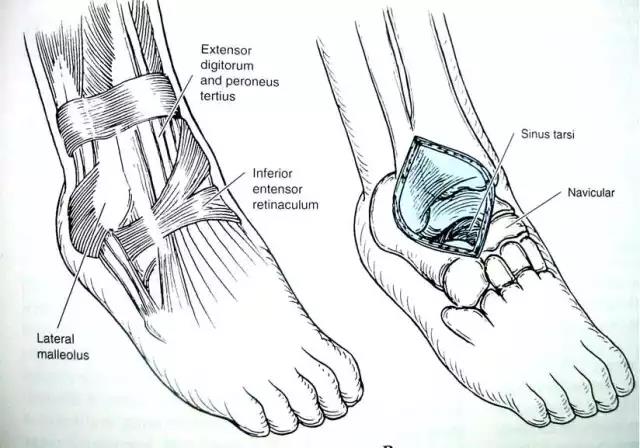

3前外入路

4后外侧入路

长屈肌腱和腓骨肌肌腱间显露